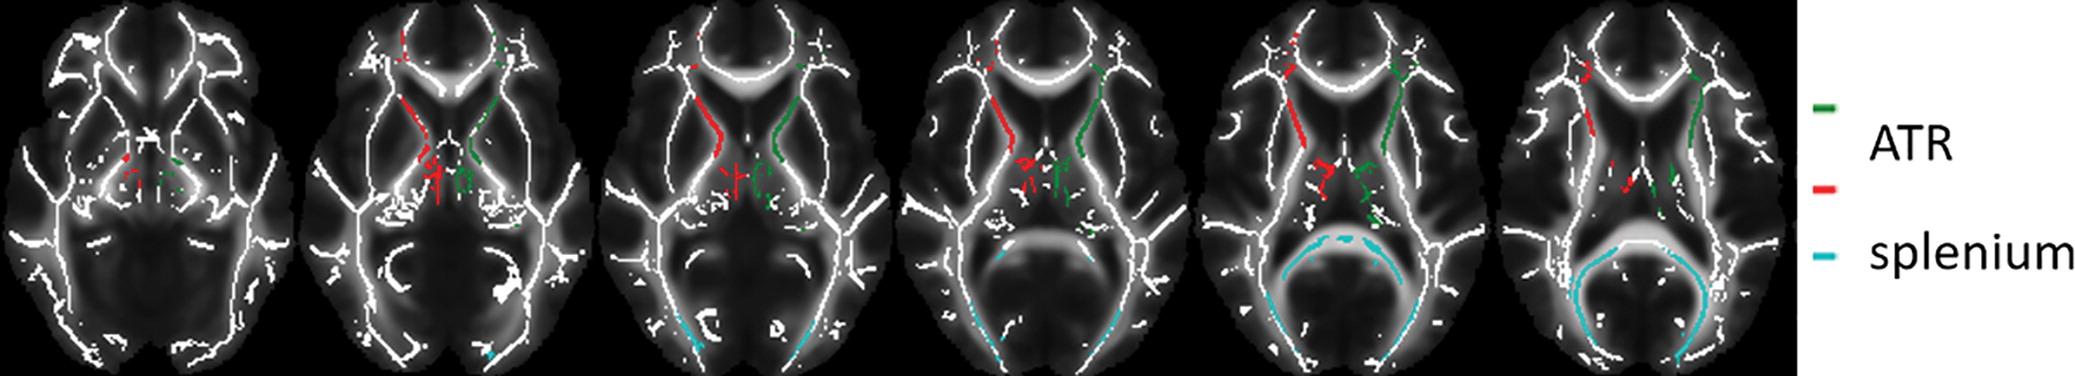

Images of regions of interest (colored lines) in the white matter skeleton representation. Data from left and right anterior thalamic radiation (ATR) were averaged. Image courtesy of C. Bouziane et al.

Patients received either MPH or a placebo for 16 weeks. Before and one week after treatment cessation, the participants underwent magnetic resonance imaging (MRI) including diffusion tensor imaging (DTI), a technique that helps assess white matter. DTI provides a measure called fractional anisotropy (FA), which is thought to reflect important aspects of white matter such as nerve fiber density, size and myelination — the process of coating nerve fibers to protect the nerve and help it carry signals more efficiently.

In boys with ADHD, four months of treatment with MPH was associated with increased white matter FA. The effects were age-dependent, as they were not observed in adults treated with MPH.